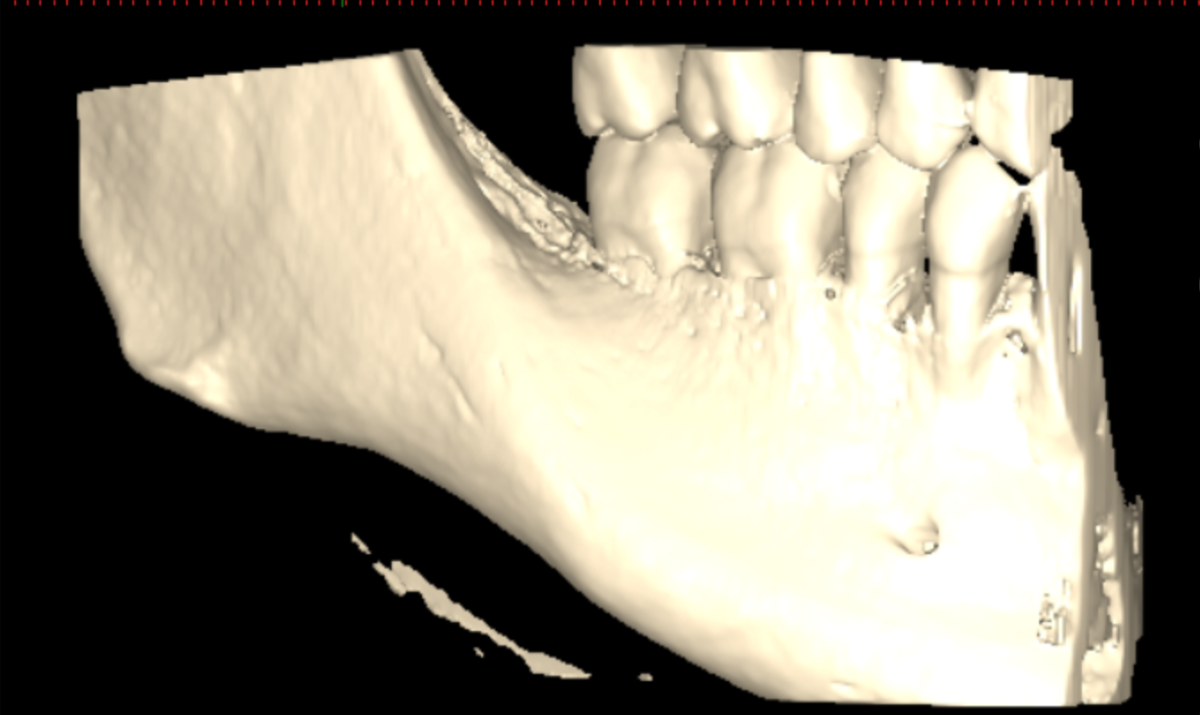

Я сделал клкт сектора 4-5-6-7 зубов справа снизу, могу приложить, если нужно. Я проходил ортодонтическое лечение, после которого у меня случилась рецессия десны на передних нижних зубах, вплоть до клыков. На самом оголоенном участке 1-2 была пластика десны пару лет назад, стало лучше. Удалены все 4 зуба мудрости